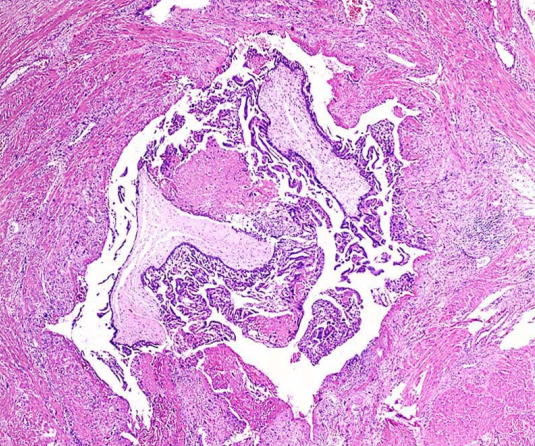

侵蚀性葡萄胎的大体检查可见子宫肌层内有大小不等的水泡状组织,宫腔内可以没有原发病灶。当病灶接近子宫浆膜层时,子宫表面可见紫蓝色结节。病灶也可穿透子宫浆膜层或侵人阔切带内。镜下可见水泡状组织侵人肌层,有绒毛结枃及滋养细胞增生和异型性。但绒毛结构也可退化,仅见绒毛阴影。

侵蚀性葡萄胎大体观 侵蚀性葡萄胎镜下观(100×)

子宫肌层见水泡状胎块组织浸润性生长